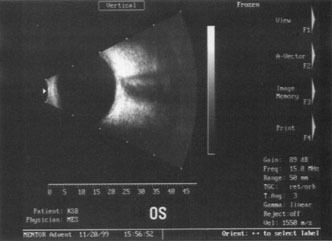

B-SCAN ULTRASOUND.

A mature cataract precludes visualization of the fundus. A B-scan ultrasonographic examination provides a real-time, two-dimensional (2D), cross-sectional image of the globe along the marked axis of the probe (Fig. 3). Cataracts are more common in patients with chronic retinal detachment, prior trauma, or intraocular tumors; therefore, a B-scan study is helpful in excluding structural posterior segment pathology before surgery on a mature cataract. Although a negative result to B-scan evaluation is reassuring, the surgeon should remember that it does not predict postoperative visual outcome. The B-scan can be thought of as a picture of Cincinnati from an airplane; the office buildings may all be standing, but you cannot tell whether the people in them are working.

Fig. 3. This B-scan ultrasound shows a normal looking posterior pole, without retinal detachment or intraocular mass. The vitreous cavity is echo lucent.